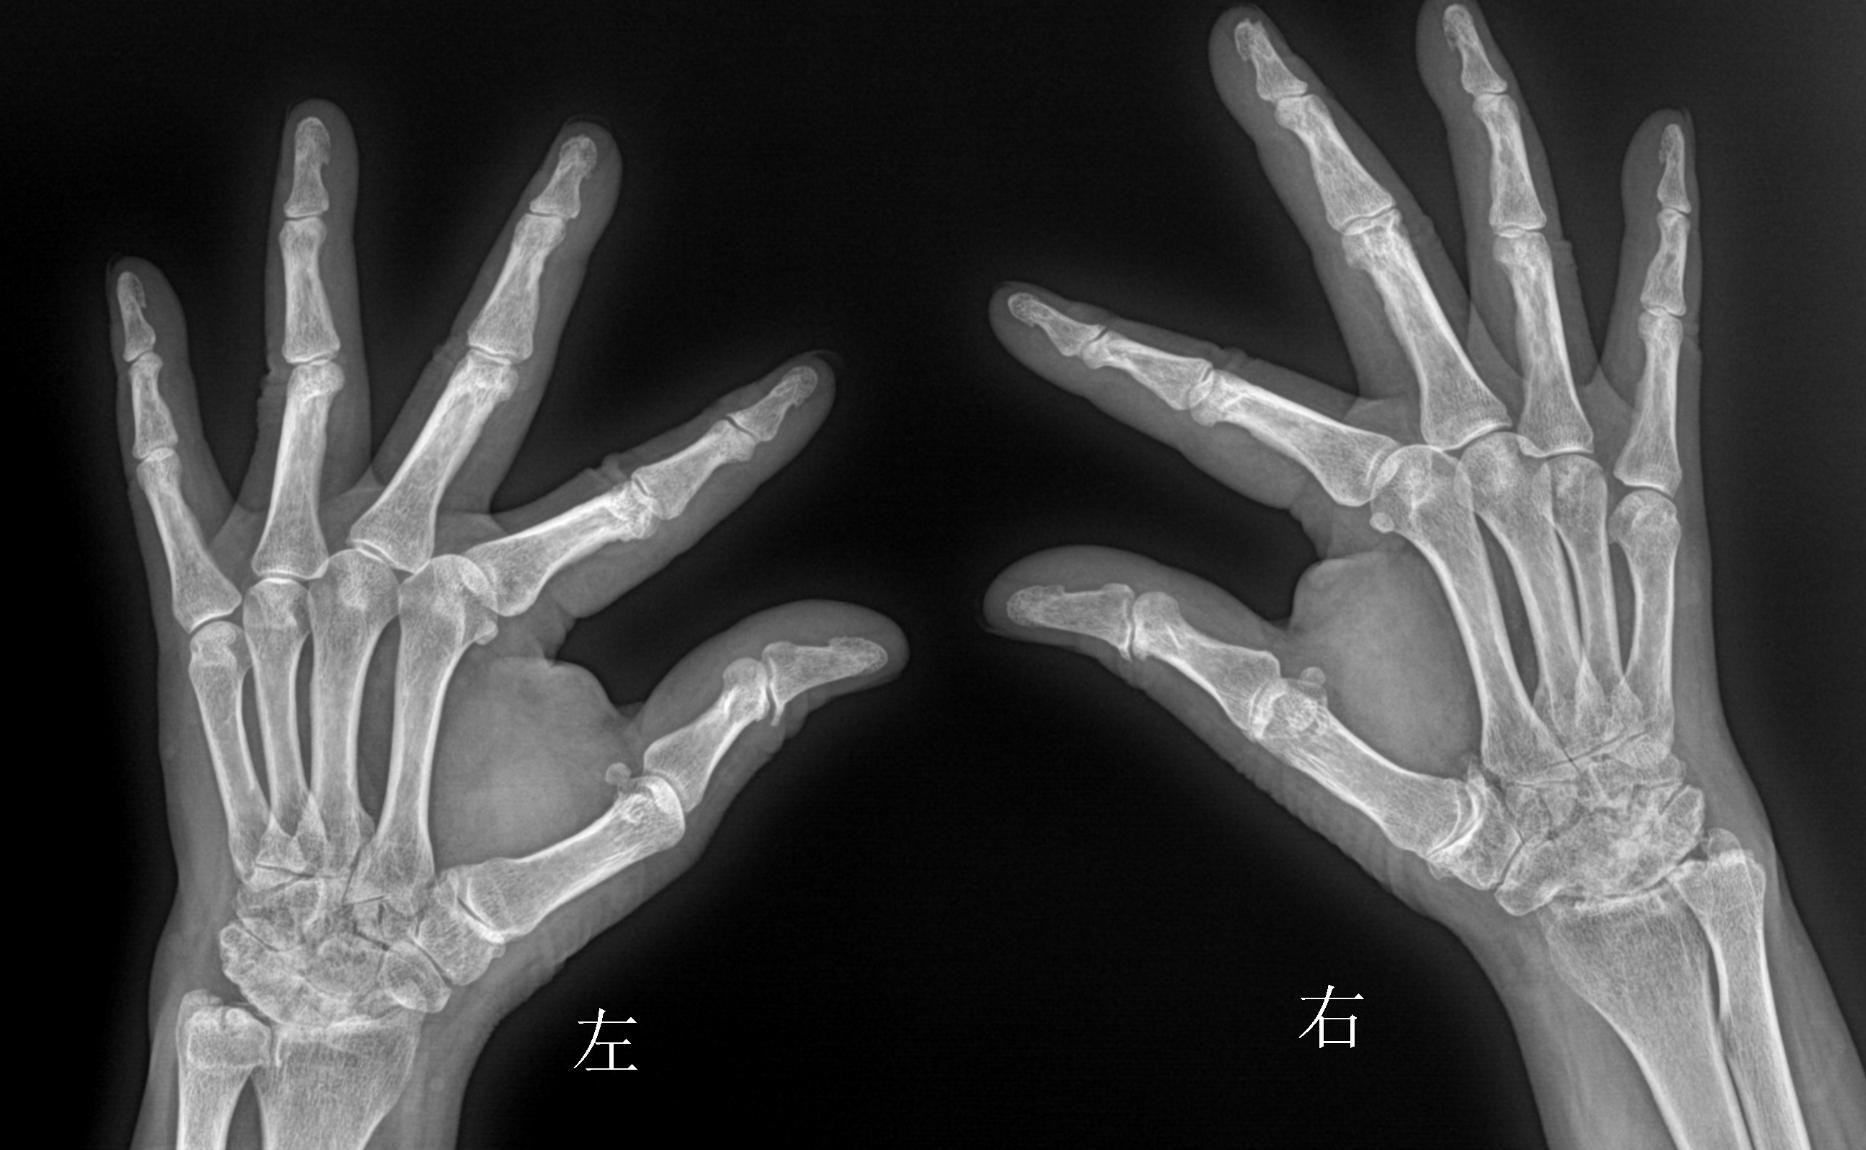

- 关节畸形 ——如果病情发展到晚期,类风湿关节炎患者会出现多种关节畸形,最常见的在手指关节(天鹅颈、纽扣化等畸形)和脚趾关节(拇外翻等畸形),膝、肘、肩关节也可因结构破坏而变形,严重者病变关节失去活动能力。